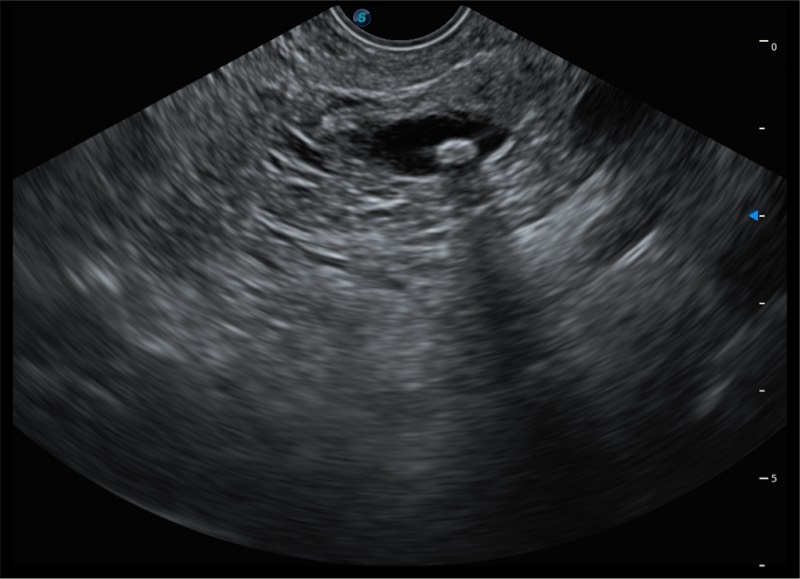

• 搭载百万级CMOS成像技术

• 及自主研发凸阵换能器,

• 可呈现优质的内镜和超声画面